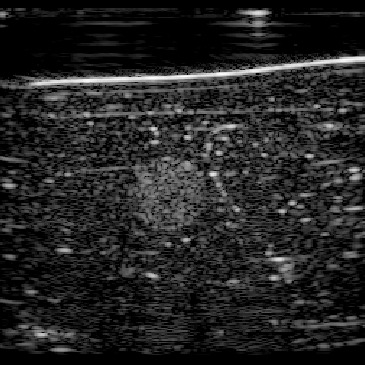

In this section, we test the trained networks on a dataset acquired from the CIRS multi-modality breast phantom. The phantom consists of an anechoic skin layer on top (directly below the transducer). Directly below the skin layer is the breast tissue mimicking layer with hyperechoic characteristics with randomly mixed embedded fibers. Hereafter, we will refer to this layer as background tissue. Inside the tissue-mimicking layer, there is an embedded hyperechoic inclusion with SoS contrast from the background layer. We do not have the SoS GT map for this phantom but based on the information provided by the manufacturer the SoS values in this phantom are in the range , where the skin layer has the lower SoS and the inclusion has a higher SoS contrast compared to the background.

Figure 12 shows the predicted SoS values for all three setups. Since the exact SoS GT is not available, from this point on we are going to use the relative SoS values to compare the results: